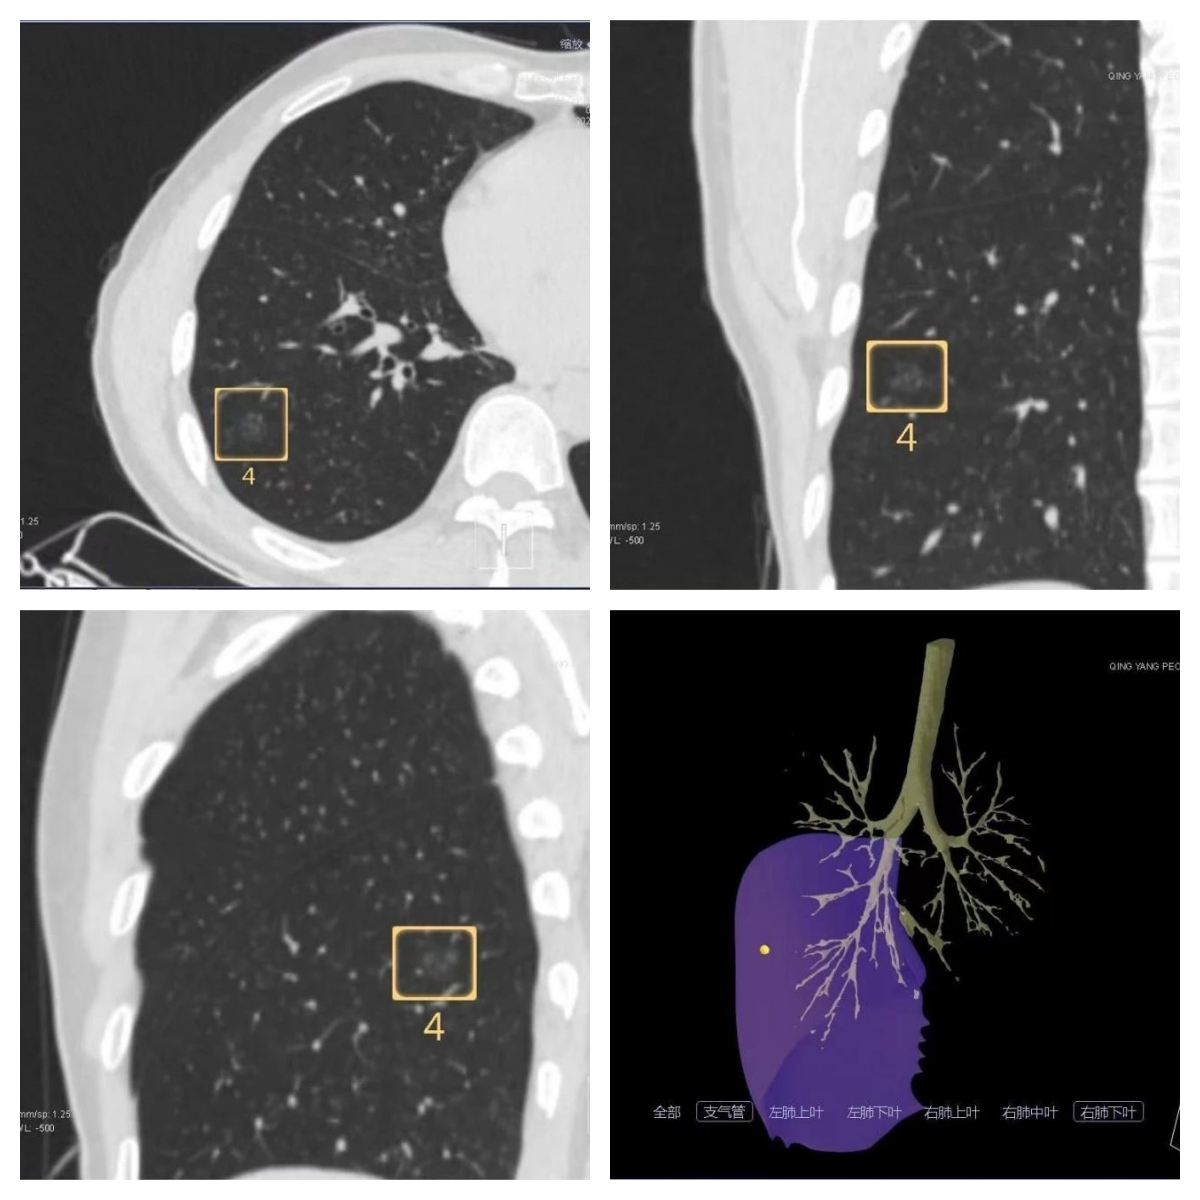

病例CT掃描,肺小結(jié)節(jié)病變?nèi)S重建

二、CT引導下肺結(jié)節(jié)穿刺定位術(shù)怎么實施?

在胸腔鏡肺小結(jié)節(jié)手術(shù)前,由醫(yī)學影像中心團隊應用CT引導實施肺穿刺,推注標記物“彈簧圈”,將“彈簧圈”頭端鉤于肺小結(jié)節(jié)病灶處,尾端留于肺表面,進行輔助定位,以便外科醫(yī)生在術(shù)中根據(jù)標記物范圍實施肺小結(jié)節(jié)精準切除。

CT引導肺結(jié)節(jié)穿刺定位